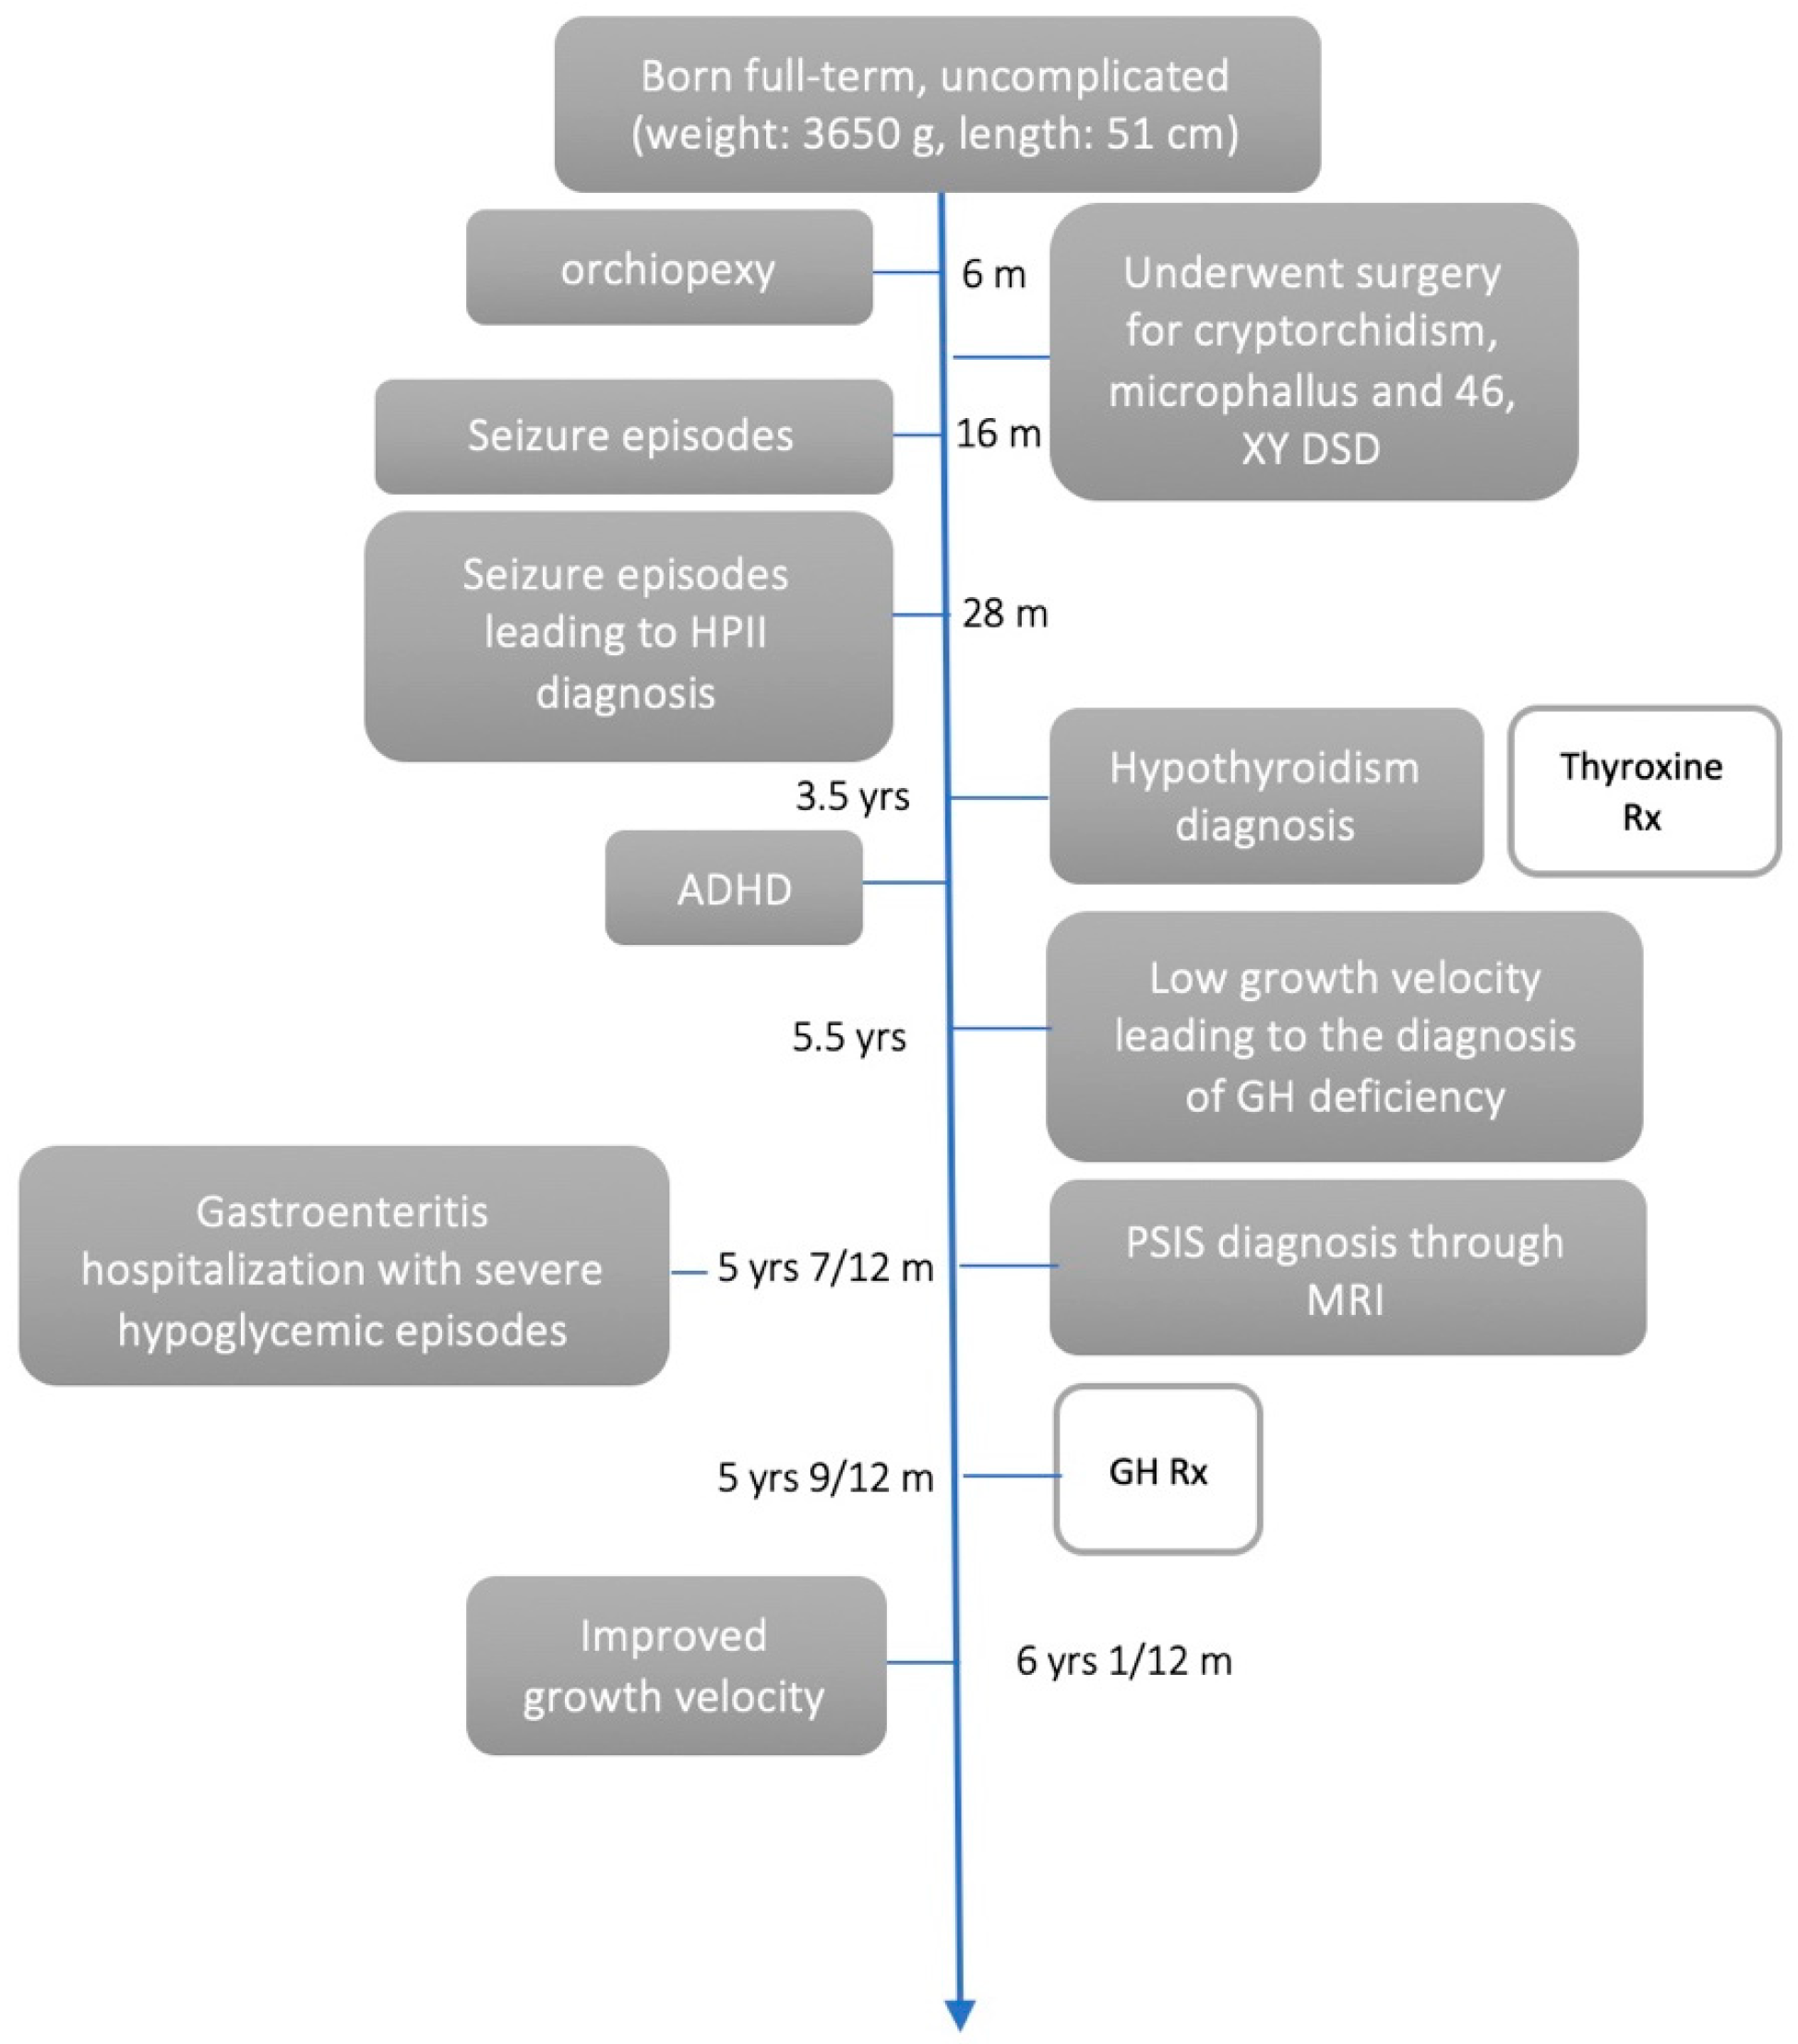

2. Case Presentation

2.1. Clinical Findings/Diagnostic Assessment

2.2. Therapeutic Intervention

2.3. Outcome and Follow-Up (10 Months)